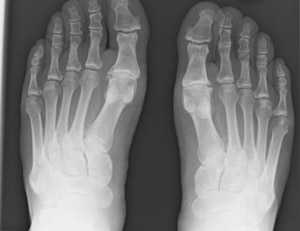

- Рентгенография кистей рук. Является основным инструментальным исследованием при артрозе. На снимках определяется уменьшение высоты суставной щели, остеосклероз субкортикальной кости, кистозные просветления, участки некроза, костные разрастания.

Обязательными клиническими критериями артроза являются боли в конце дня, а также боли, возникающие после нагрузки и уменьшающиеся в покое. Перечень обязательных рентгенологических критериев включает остеосклероз и сужение суставной щели. В качестве дополнительного признака рассматриваются костные разрастания, определяемые визуально и с помощью рентгенологического исследования. Количество припухших (воспаленных) суставов должно быть менее 3.

- На 1 стадии на рентгеновском снимке наблюдается минимальное сужение суставных щелей с незначительным заострением краевых поверхностей костей.

- На 2 стадии сужение суставных щелей носит уже выраженный характер, заметно возникновение остеофитов, мелкие трещины костей, часто - кисты.

- На 3-й стадии рентгенография демонстрирует полное смыкание суставных щелей, уплотнение костных поверхностей с выраженной деформацией, крупные кисты, фрагменты тканей в суставе (суставные мыши).